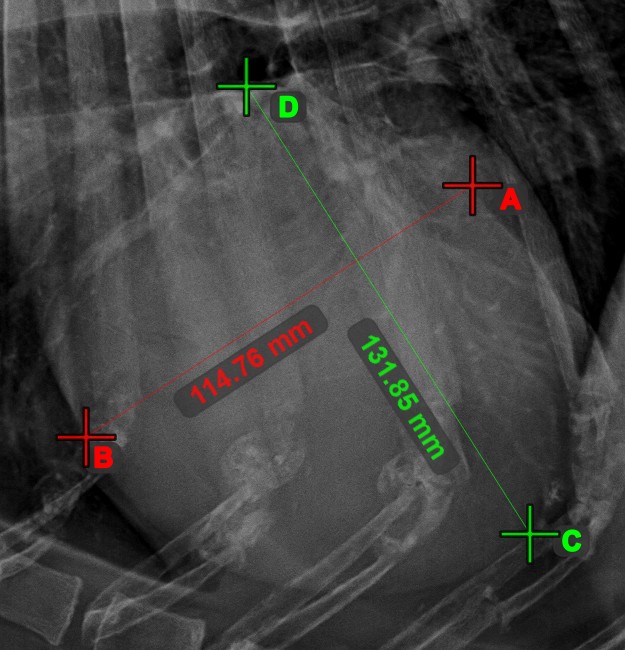

Line Intersection¶

Quickly and accurately locate and mark the intersection point between two existing lines by using the Line Intersection

tool.

Select the tool from the left toolbar and assign it to one of the available mouse buttons. Select two lines that have already been drawn on the scene to complete the measurement. The intersection point of the line will be automatically calculated and marked on the scene. The intersection point of two lines will always be marked with the letter X.

Information

If two lines do not intersect directly, the intersection point of their extended projections on the scene will be marked.

Line Measurement¶

Select the Line Measurement

tool and assign it to one of the available mouse buttons. Place the start and end points on the scene or select them from already existing points on the image. The distance between the two points will be automatically

calculated by using the default calibration data, or the recalibrated data by the length calibration measurement.